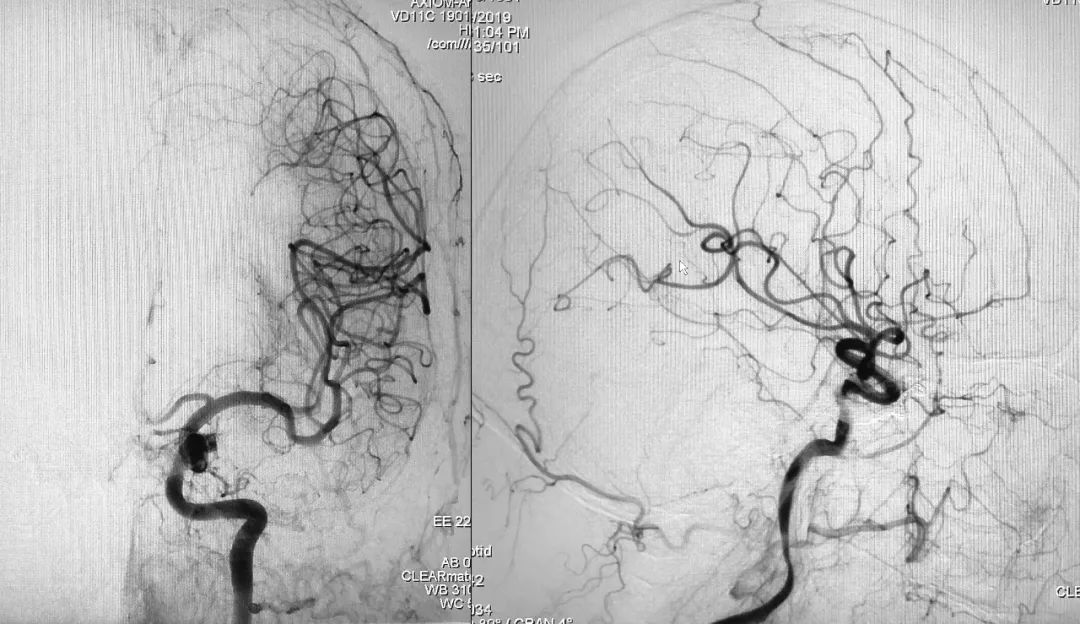

右侧颈总动脉正、侧位造影:

左侧颈总动脉正、侧位造影: